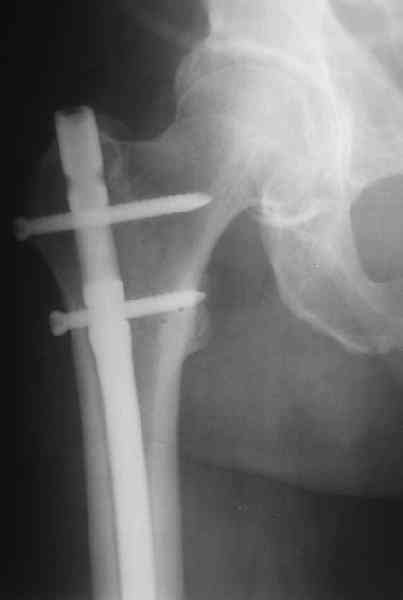

Дополнительные доступы для введения гвоздя и проксимальных винтов понадобились, но они маленькие, по 1 см. Нижние винты ввели прямо между швами. Суставы дополнительно не травмировали, и даже ввели гвоздь не через f. piriformis, а через большой вертел.

Длину восстановили, возможно, даже с изьбытком, ну да динамизируем пораньше. Введенные в овальное отверстие дистальые винты имеют угловую стабильность. Снимки приложены. Заранее спасибо за критику и комментарии.